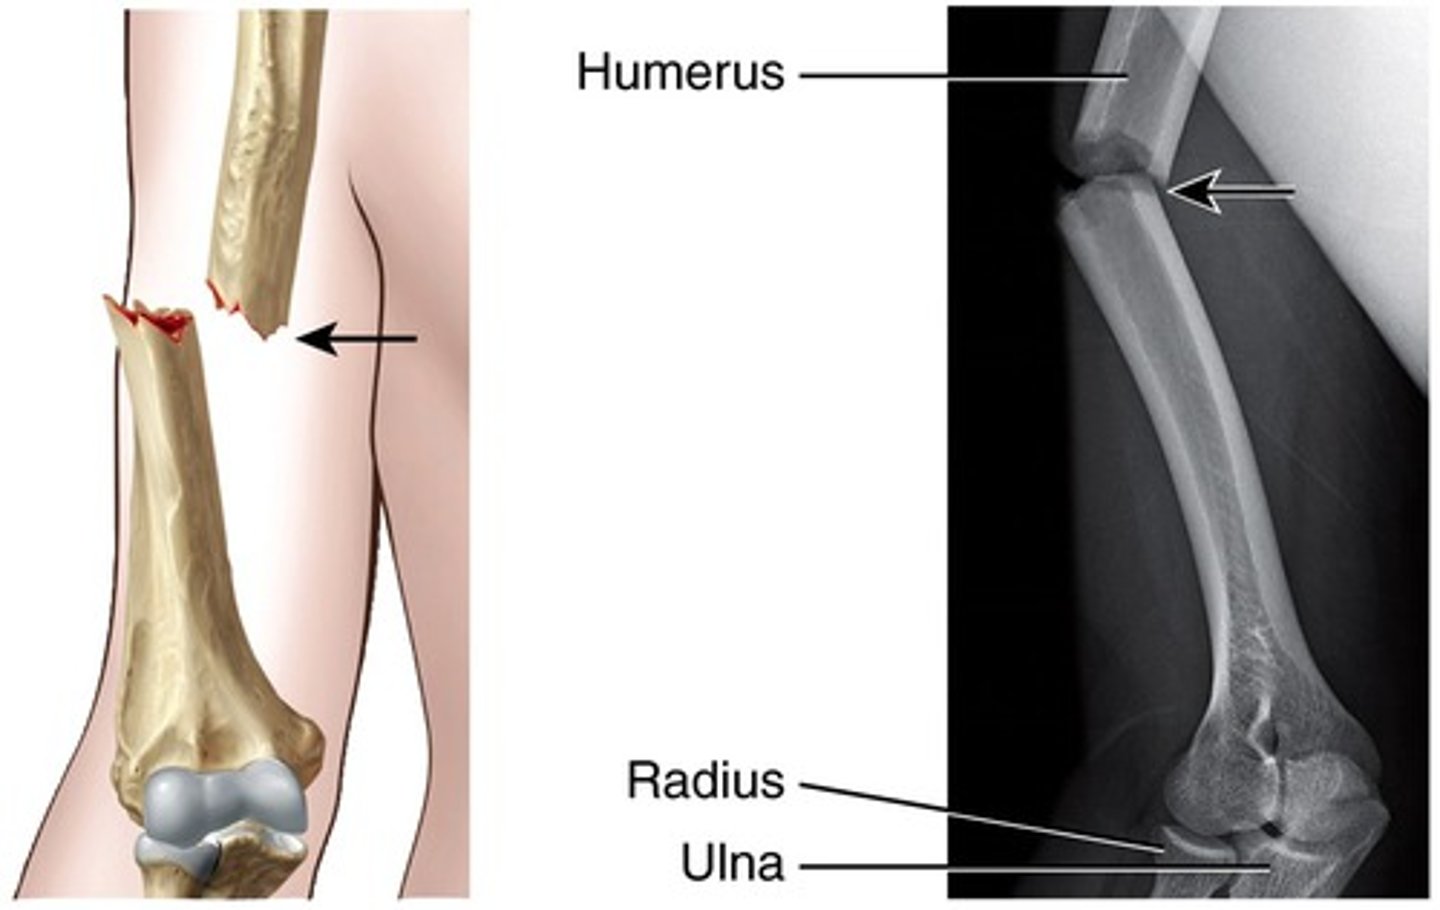

Fracture of proximal half of ulna with dislocation of radial head

Monteggia fx